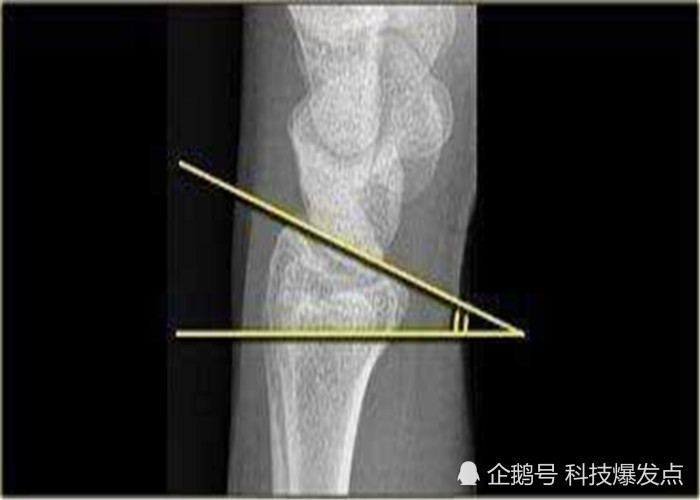

法贝骨是什么呢?

法贝骨原本是属于膝盖骨当中的一块籽骨,由于在人体

法贝骨,一般在哺乳动物的身上比较常见,尤其是灵长

在19世纪70年代的时候,科学家们首次发现了法贝骨的